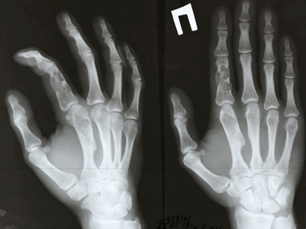

Хондрома — опухоль детского и юношеского возраста. Вовлекаются чаще короткие трубчатые кости кисти и стопы. К хондромам следует относиться как к потенциально злокачественным опухолям. Хондромы разделяют на энхондромы и экхондромы • Энхондрома — опухоль, располагающаяся внутри кости. В центре вздутого одиночного очага — гомогенное просветление неправильной округлой или овальной формы с чёткими контурами. На его однородном фоне обнаруживают единичные тени очагов обызвествления хряща •

• Локализация: в 50% поражаются кисти и стопы

Энхондрома — это доброкачественная внутрикостная опухоль, состоящая из хрящевой ткани. Чаще всего возникает на коротких косточках кисти или стопы, в основном ближе к одной из суставных поверхностей, но иногда может распространяться и на всю фалангу.

Как правило, энхондрому выявляют случайно — например, на рентгеновских снимках, или когда уже случился перелом кости, внутри которой было это образование. Опухоль истончает кость, и вероятность переломов возрастает.

утолщение или деформация фаланги пальцев

небольшое утолщение на пястной кости или фаланге.

Для диагностики энхондромы достаточно рентгеновских снимков. В редких случаях может потребоваться компьютерная томография (КТ) и консультация онколога.

Энхондромы имеют вытянутую, овальную форму и имеют четкие границы.

Рентгенография и компьютерная томография

При крупных поражениях, зона просветления окружена эндостальным склерозом с истончением и вздутием коры, при этом компьютерная томография позволяет оценить целостность кортикального слоя. Кальцификация в поражении варьирует от точечных до кольцевидных. При локализации в фалангах, энхондромы характеризуются экспансивным литическим ростом. При других локализациях проявляются экспансивным ростом с характерной картиной в виде колец или арок за счет кальцинатов. Типично, энхондромы представляет собой небольшое 1-2 см лирическое поражение без признаков агрессивности: